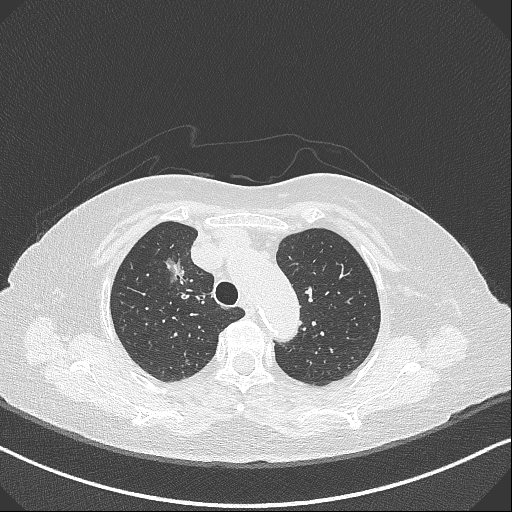

陳婆婆于4月29日因檢查發(fā)現(xiàn)肺占位性病變4+月入住我科,經(jīng)術(shù)前相關(guān)檢查,手術(shù)切除肺結(jié)節(jié)的指針明確。然而為90歲高齡患者動(dòng)肺結(jié)節(jié)手術(shù),對(duì)手術(shù)團(tuán)隊(duì)是一個(gè)巨大考驗(yàn)。